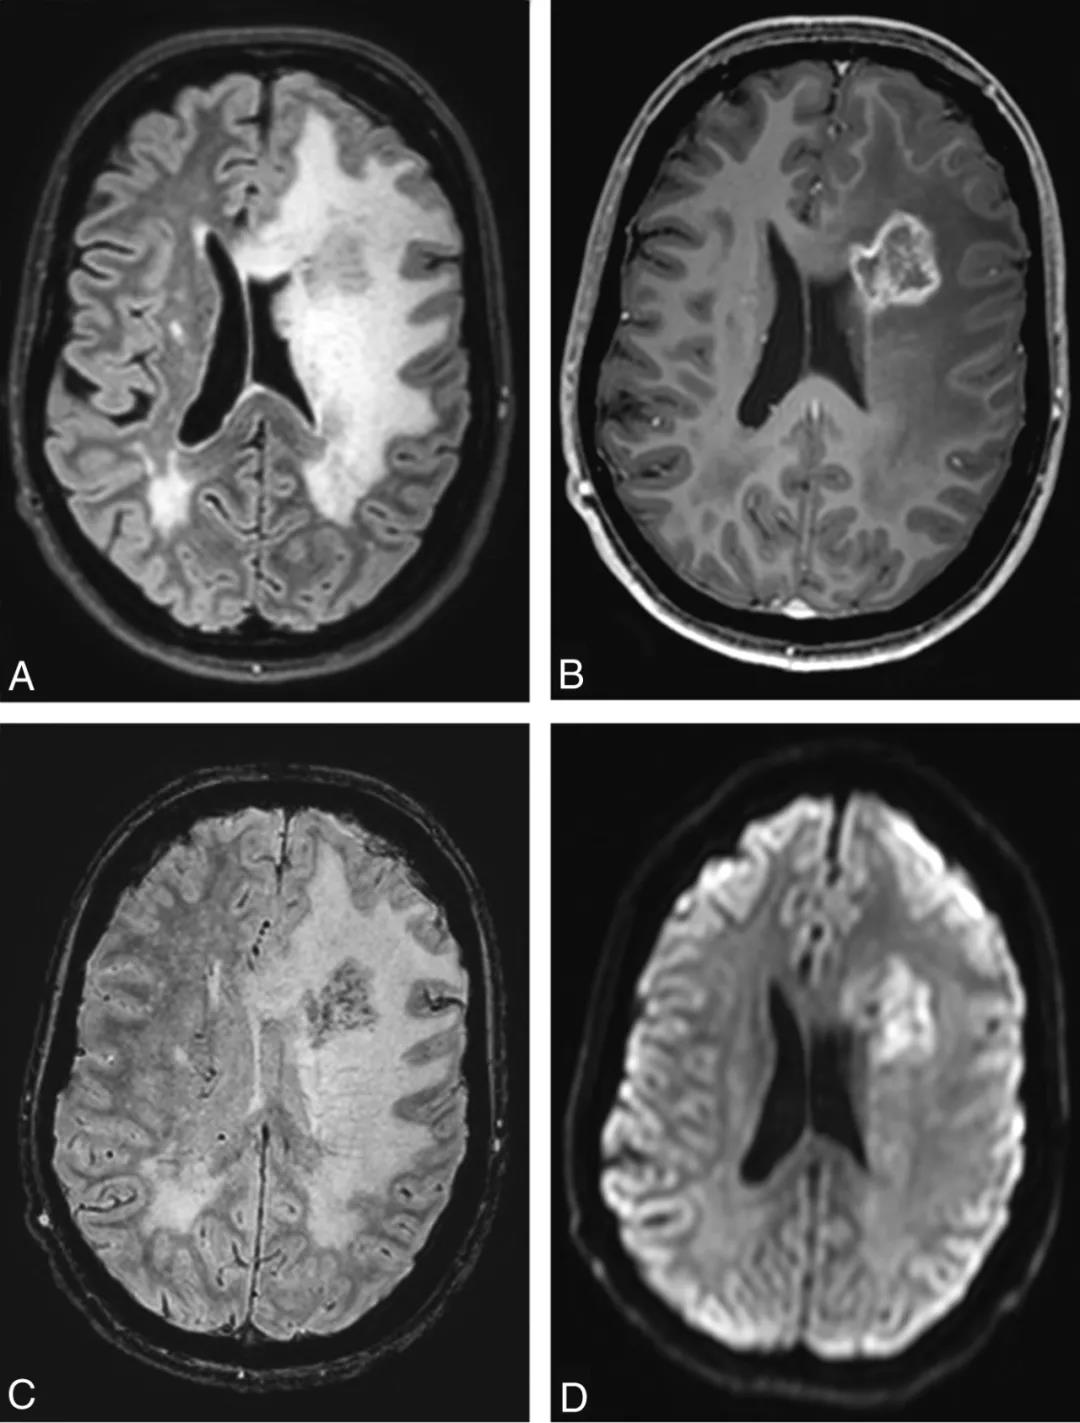

图4 45岁女性假瘤的影像学特征。直径30mm的环形强化病变,位于左侧额角外侧,病变中心可见多个点状磁敏感伪影和弥散抑制,周围广泛血管源性水肿伴占位效应(a,FLAIR. B,3DT1Gd. C,SWI. D,DWI)。